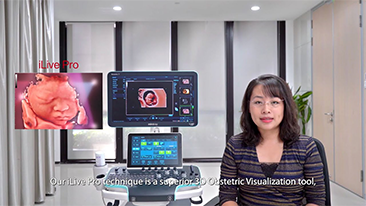

Kad?n sa?l??? tarama ziyaretlerinde yĂŒksek dĂŒzeyde hasta hacimlerini desteklemek i?in, optimize edilmi? OBG i? ak??lar? gerekir. ?rne?in, merkezi sinir sistemi (CNS) malformasyonlar?, en yayg?n g?rĂŒlen konjenital anormalliklerden biridir. K?tĂŒ fetĂŒs pozisyonu gibi, ?e?itli g?rĂŒntĂŒleme durumlar? nedeniyle, 2 boyutlu ultrasonda MSPâyi elde etmek ?zellikle zordur. Bu nedenle, otomatik alg?lama ve ?l?ĂŒmler, tarama verimlili?ini bĂŒyĂŒk ?l?ĂŒde art?rabilir.